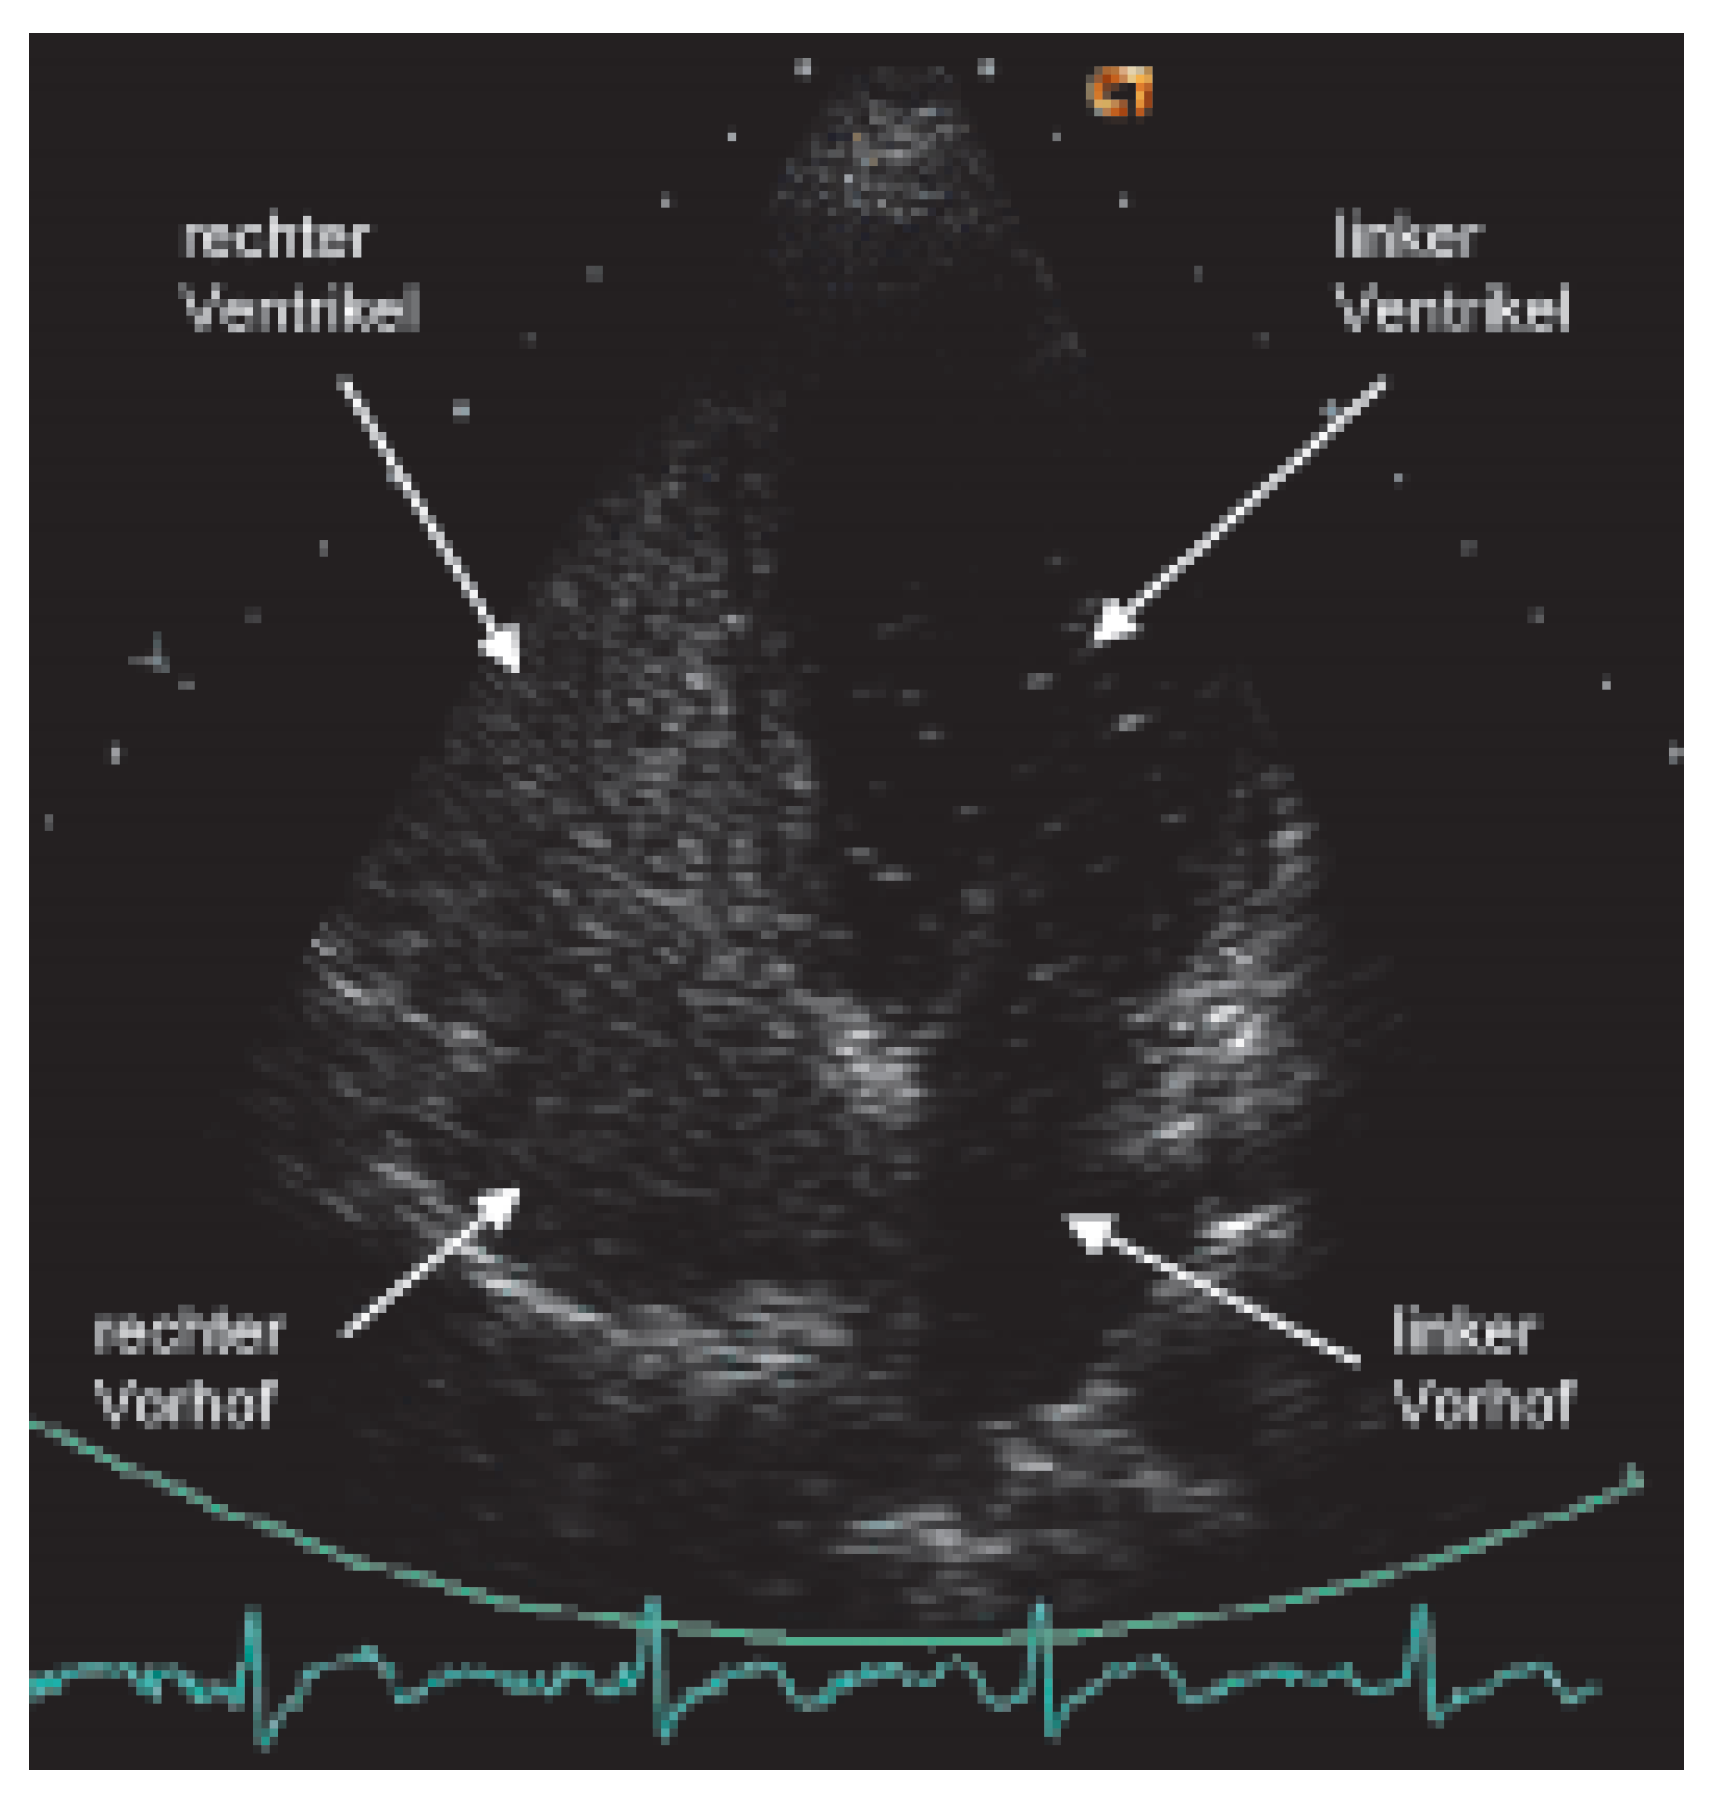

Sind die erwähnten Artefakte sowie pulmonale Erkrankungen ausgeschlossen, so muss an ein zyanotisches Herzvitium gedacht und ein Rechts-Links-Shunt gesucht werden. Ergibt sich aus der normalen transthorakalen Doppler-echokardiographischen Untersuchung noch keine Diagnose, so wird ein Echokontrastmittel (am besten aus Luft und physiologischer Kochsalzlösung hergestellte «Bubbles») von einer Vene der oberen Extremität injiziert (Figure 1). Allenfalls kann der Rechts-Links-Shunt nur nach Provokation mittels eines korrekten Valsalva-Manövers nachgewiesen werden. Führt die Injektion von Bubbles auch nicht zur Diagnose, das heisst, findet kein Übertritt von Bubbles in die linken Herzhöhlen statt, so wird die Untersuchung mit Injektion von Bubbles von der unteren Extremität wiederholt. Treten die Bubbles nun nur im linken Vorhof auf, so kann die Diagnose einer in den linken Vorhof mündenden Vena cava inferior gestellt werden [10]. Ist auch dieser Untersuch negativ, das heisst, ein RechtsLinks-Shunt ist ausgeschlossen, so muss in einem dritten Schritt ein abnormes Hämoglobin (z.B. CO-Hämoglobin bei CO-Intoxikation; Anteil des CO-Hämoglobins ist mit vielen Blutgas-Messgeräten bestimmbar) oder eine Hämoglobinopathie gesucht werden. Zu erwähnen ist hier z.B. das in der Schweiz vorkommende Hämoglobin Schlierbach [11]. Fällt die Sauerstoffsättigung im Stehen gegenüber derer im Liegen ab, so ist an das seltene Platypnoe-Orthodeoxie-Syndrom zu denken [12].

Figure 1. Apikaler 4-Kammerschnitt nach Injektion von «Bubbles» in die rechte Kubitalvene: Kontrastierung der rechtsseitigen Herzhöhlen mit Übertritt der «Bubbles» auf die linke Seite auf Vorhofebene.